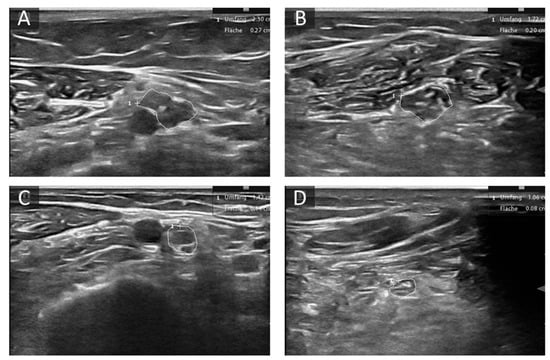

- Gamber, D.; Motte, J.; Kerasnoudis, A.; Yoon, M.S.; Gold, R.; Pitarokoili, K.; Fisse, A.L. High-Resolution Nerve Ultrasound to Assess Nerve Echogenicity, Fascicular Count, and Cross-Sectional Area Using Semiautomated Analysis. J. Neuroimaging 2020, 30, 493–502. [Google Scholar] [CrossRef]